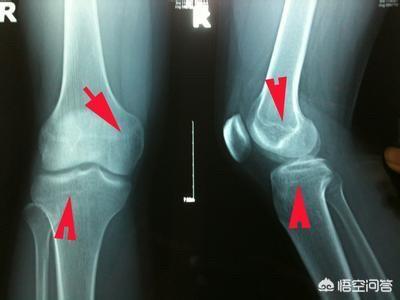

医学的には、月経後、骨端が閉じていない限り、まだ身長が伸びる余地はあります。本当に身長が伸びるかどうかを知りたいのであれば、病院に行って超音波検査で骨年齢を調べてもらうのが一番です。骨年齢が年齢を上回っていなければ、身長が伸びる可能性はあります。

したがって、女の子は1年間月経されている場合は、正常によると、すでに遅い開発である、あなたは骨年齢をチェックするために子供を取ることができ、子供の骨端が閉じているかどうかを知る、それが閉じている場合は、半年が成長しなかった、それは背の高い成長を停止することを意味します。